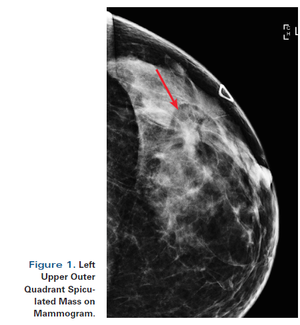

A 55-year-old perimenopausal woman presented with a palpable lump in her left breast. Diagnostic mammogram showed a 1.8-cm spiculated mass with scattered microcalcifications within the mass. Comparison with her most recent prior mammogram (about 9 months earlier) showed this to be a new mass.